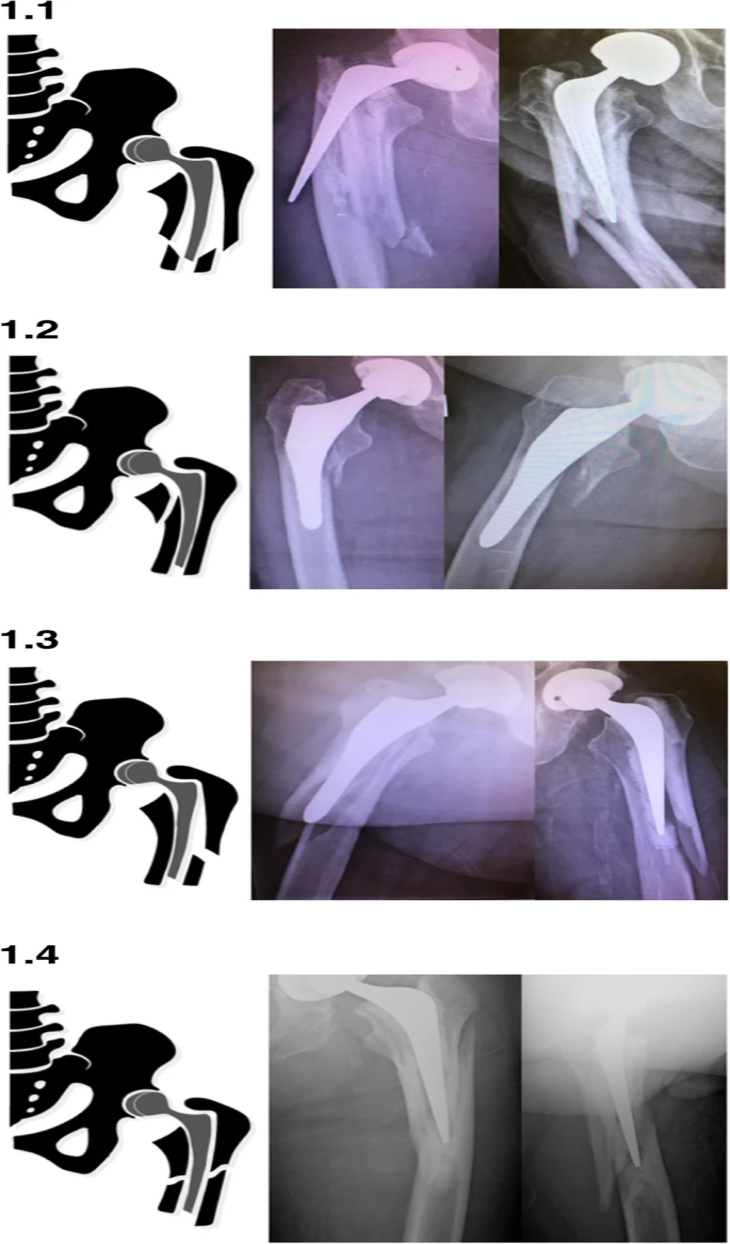

Les fractures de VancouverB2 sont classées en quatre modèles de fracture distincts : les modèles 'éclatés', en coquille et hélicoïdaux décrits précédemment, et le modèle en coquille 'inverse' nouvellement observé.Une apparence X-ray représentative de la série et la représentation graphique correspondante sont présentées (Figure 1).

Les fractures en éclatement et en spirale étaient significativement associées aux tiges cimentées, tandis que les fractures à lambeau étaient significativement associées aux tiges non cimentées.

Le motif à clapet inversé s'est produit de la même manière dans les deux tiges.

L'association des sous-types de la classification de Vancouver, y compris les quatre types de fracture B2 décrits ci-dessus, avec la géométrie de la tige reflète la tendance générale des types de fracture.